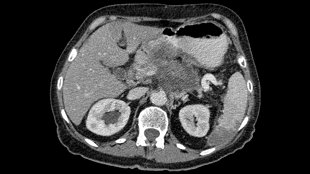

胰腺癌,圖片來自維基共享資源|Hekkerhoff